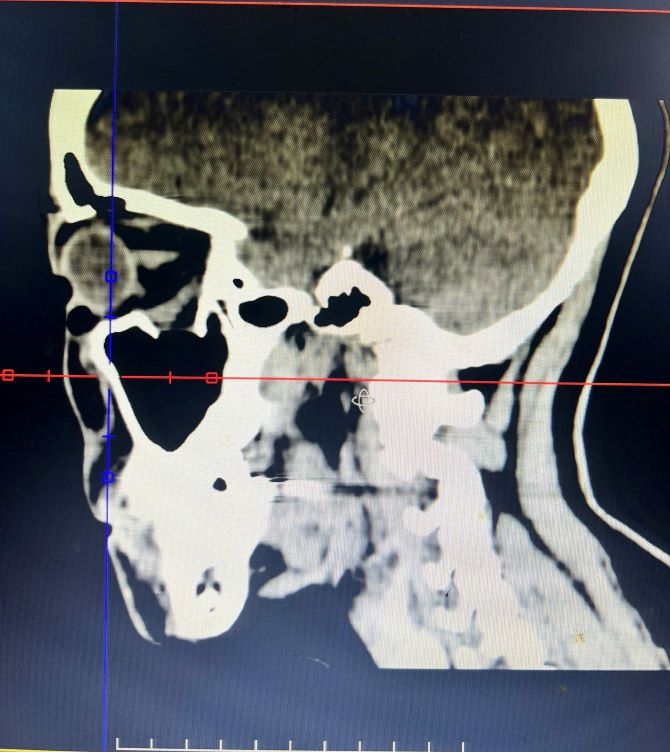

Hình ảnh chụp cắt lớp vi tính của bệnh nhân (ảnh do BV cung cấp).

Kết quả chụp cắt lớp vi tính cho thấy bệnh nhân T, bị vỡ sàn ổ mắt phải, kèm theo tình trạng tổ chức phần mềm ổ mắt thoát vị xuống xoang hàm. Đây là nguyên nhân trực tiếp gây rối loạn vận nhãn và suy giảm thị lực, nếu không được xử trí kịp thời có thể để lại di chứng lâu dài.